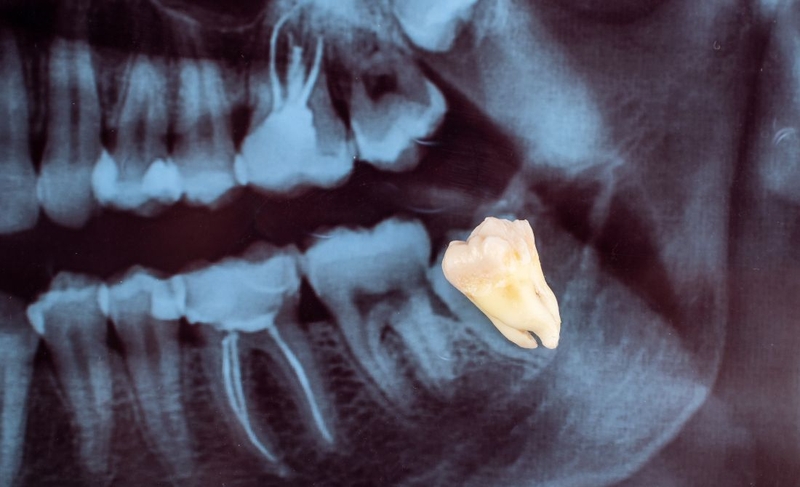

Trước tiên, bác sĩ sẽ tiến hành khám lâm sàng để đánh giá tình trạng răng miệng, vị trí mọc của răng số 8. Chụp X-quang sẽ giúp xác định chính xác vị trí, hình dạng và mối quan hệ của răng số 8 với các cấu trúc xung quanh như dây thần kinh, xương hàm.